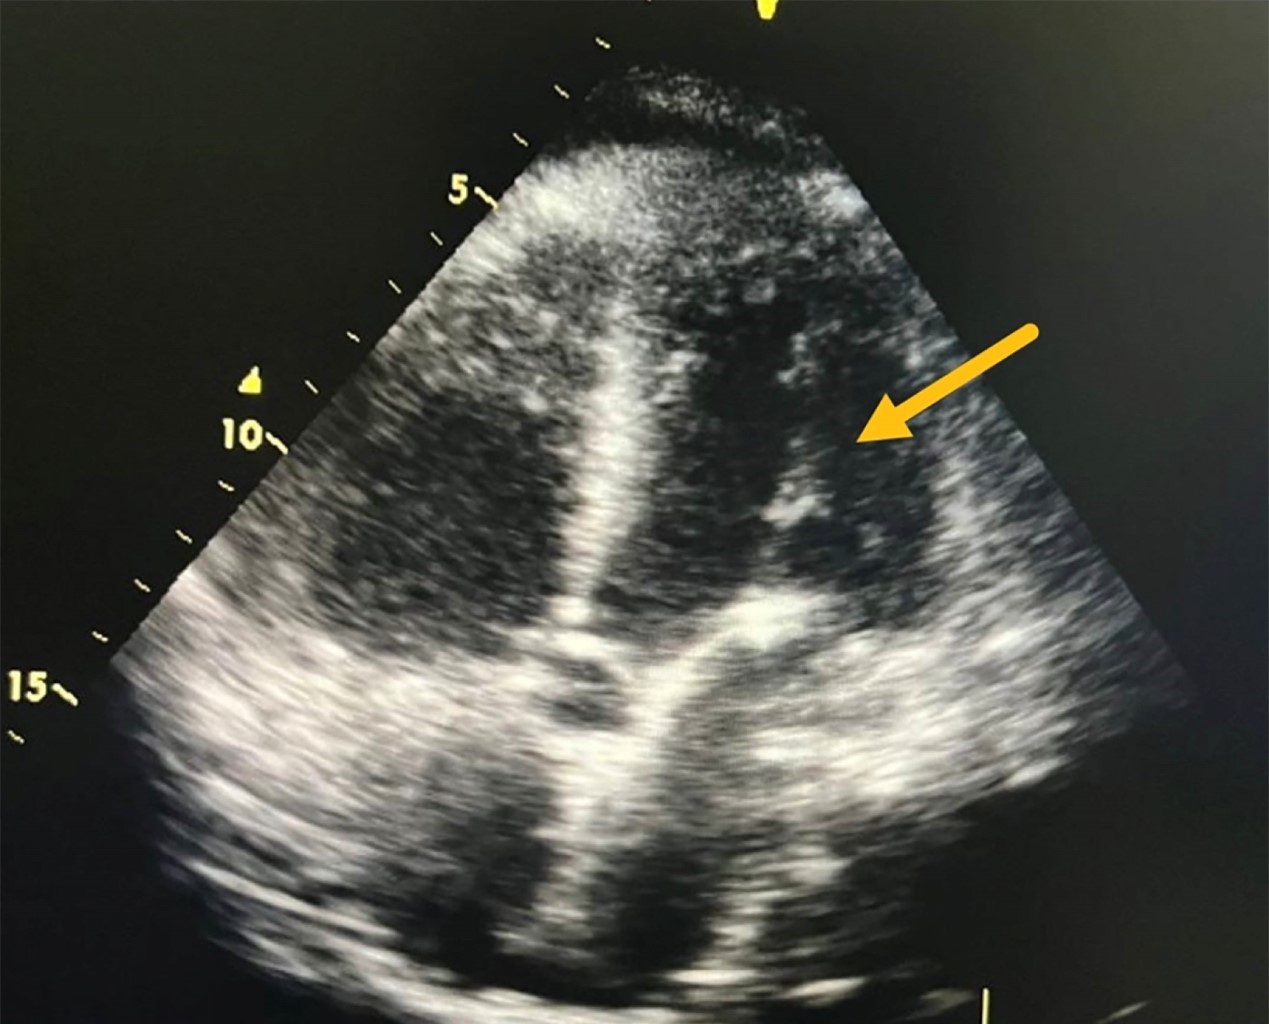

Presentamos el caso de un paciente masculino quien fue tratado en el departamento de urgencias por derrame pleural izquierdo mediante un drenaje torácico. Posterior a la colocación se obtuvo gasto hemático inmediato. Se realizó tomografía de tórax, así como ecocardiograma que evidenció posición de tubo de drenaje en ventrículo izquierdo. Se realizó intervención quirúrgica para el retiro de catéter mediante toracotomía anterior izquierda con extracción exitosa.

Figura 1